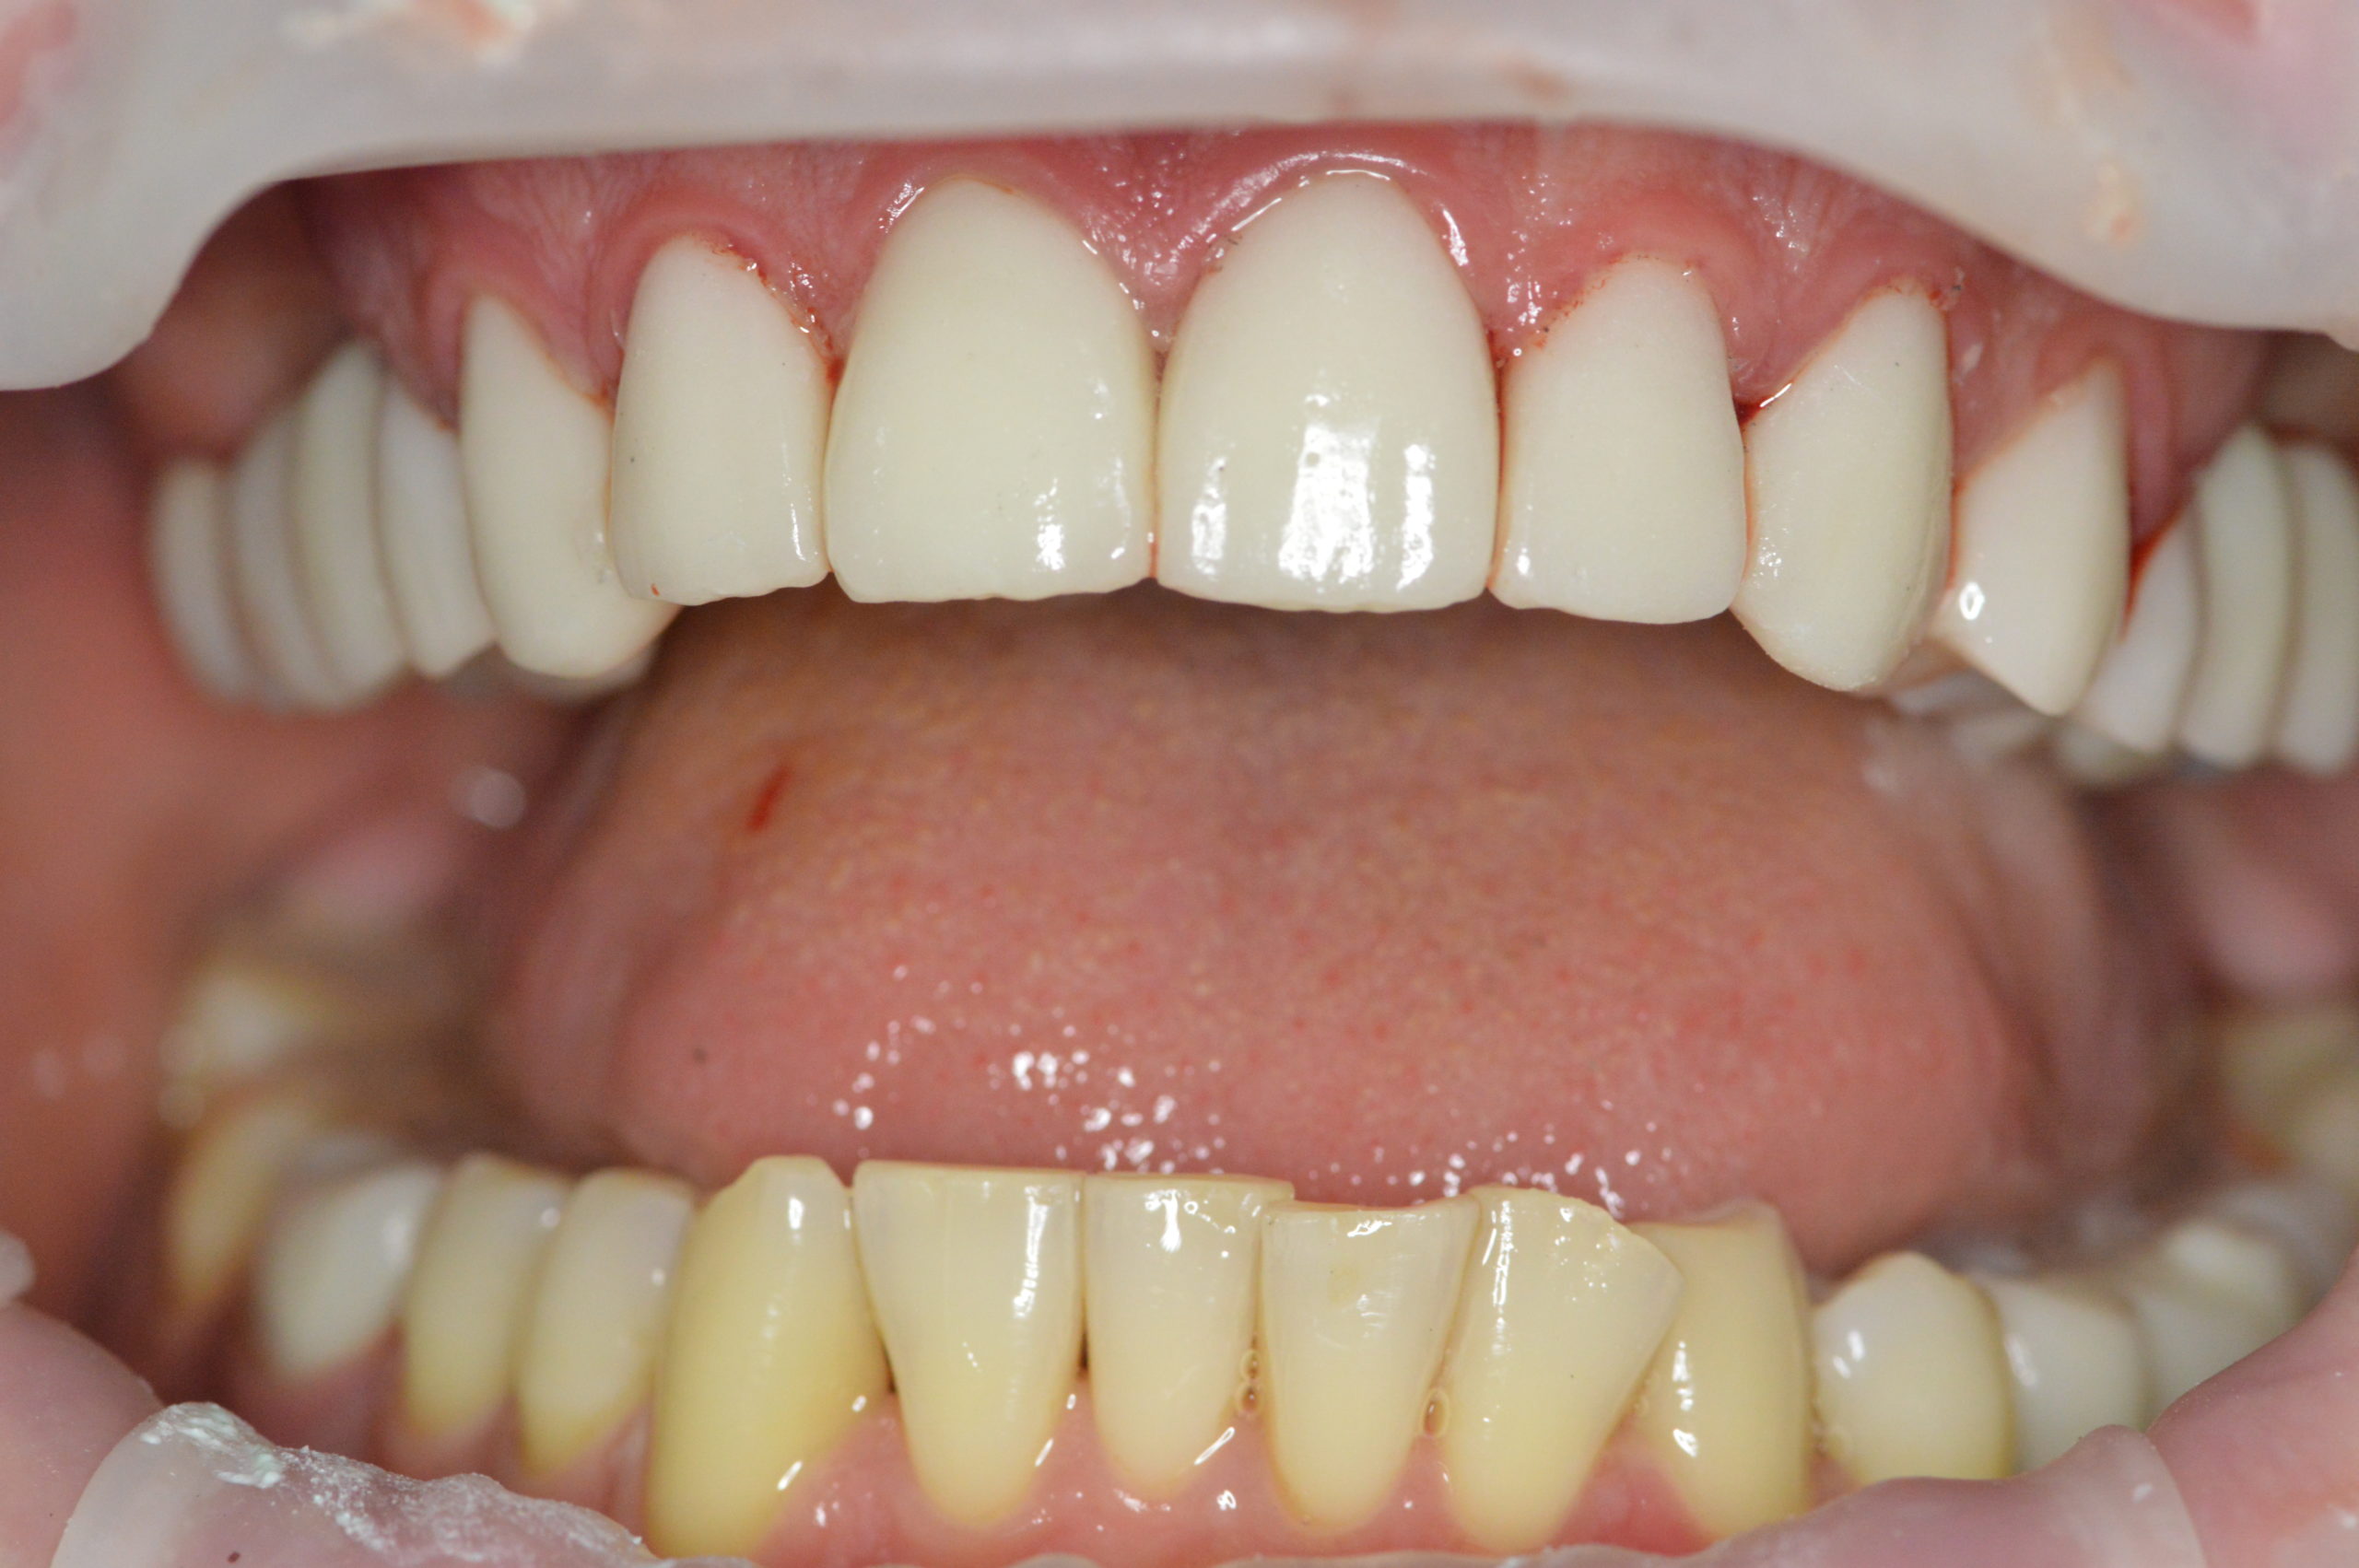

After his next visit, Mr. Peter left our clinic with this beautiful and natural looking smile. His upper jaw was fully reconstructed using dental implants in combination with dental crowns. His lower jaw was treated with 2 dental implants and two zirconium dental crowns.

Peter continues to visit our clinic to get treatment for his lower teeth. We have already done 3 fillings and one root canal treatment. We are happy that we could help Peter achieve a good looking and healthy smile.